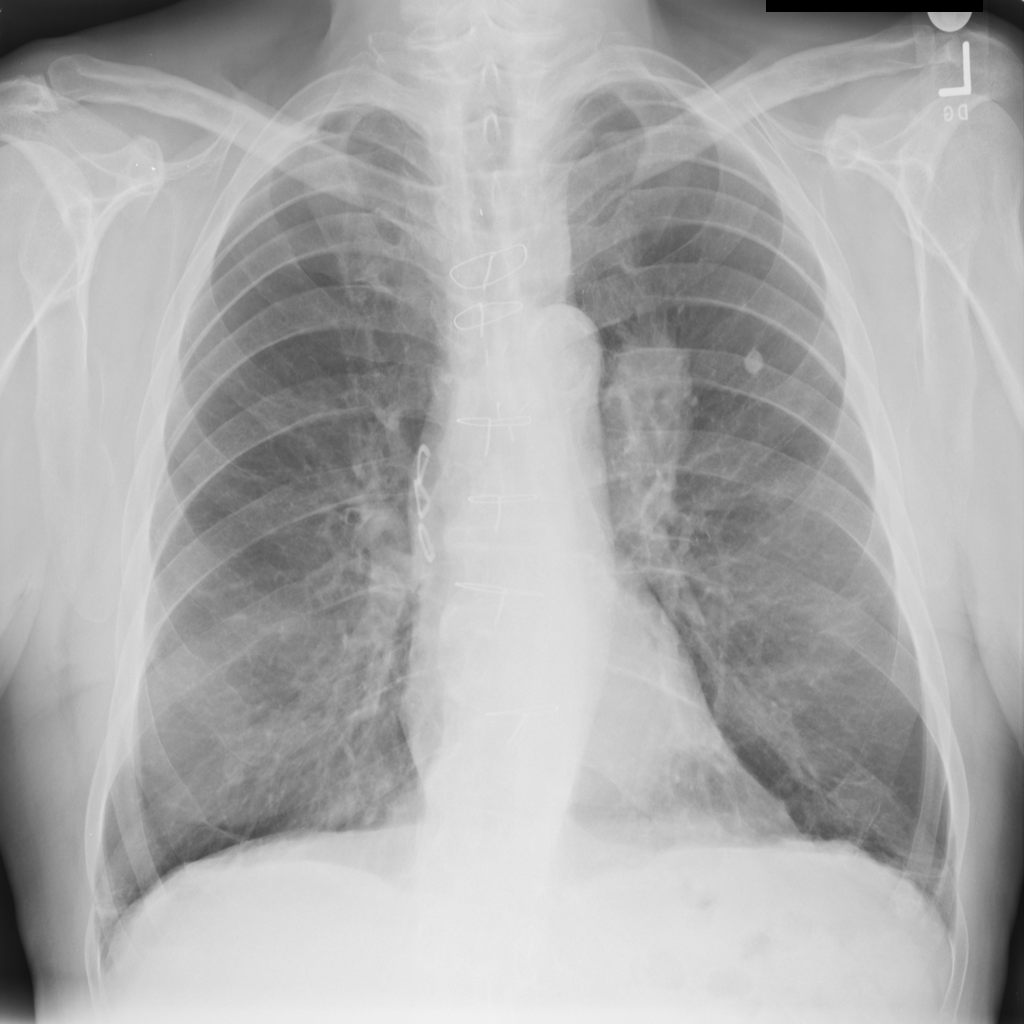

PAT-C255 · IMG-000Emphysema

PAT-C255 · IMG-000

PA